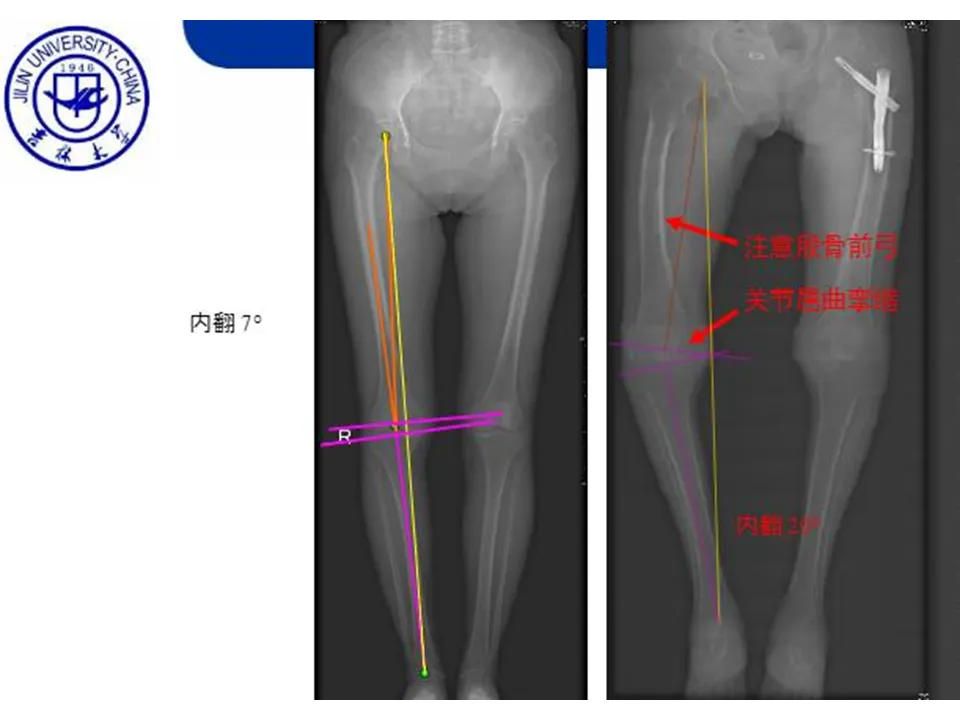

>【骨科PPT】全膝关节置换的截骨原则

【骨科PPT】全膝关节置换的截骨原则